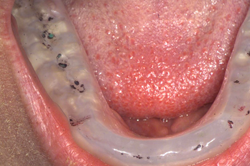

case pictures

- night guards